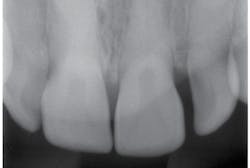

Radiographs—The teeth exhibit pulpal-root canal obliteration (see Figures 4, 5). The roots of the teeth are narrow and appear to be funnel-shaped. The crowns are large and there is constriction at the cervical neck of the tooth.